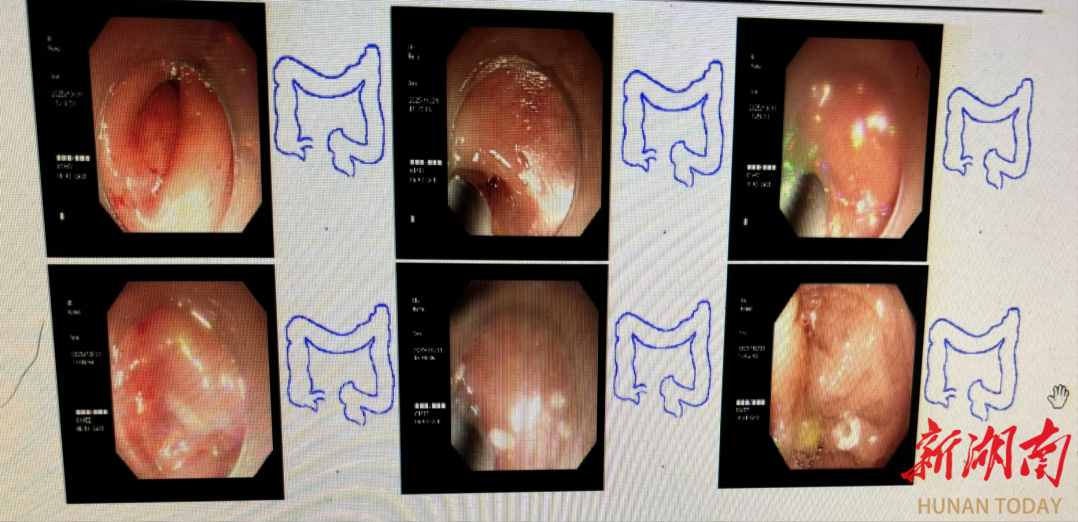

高龄≠放弃!“高定”手术方案助八旬老人告别“造瘘”恐惧,实现低位保肛